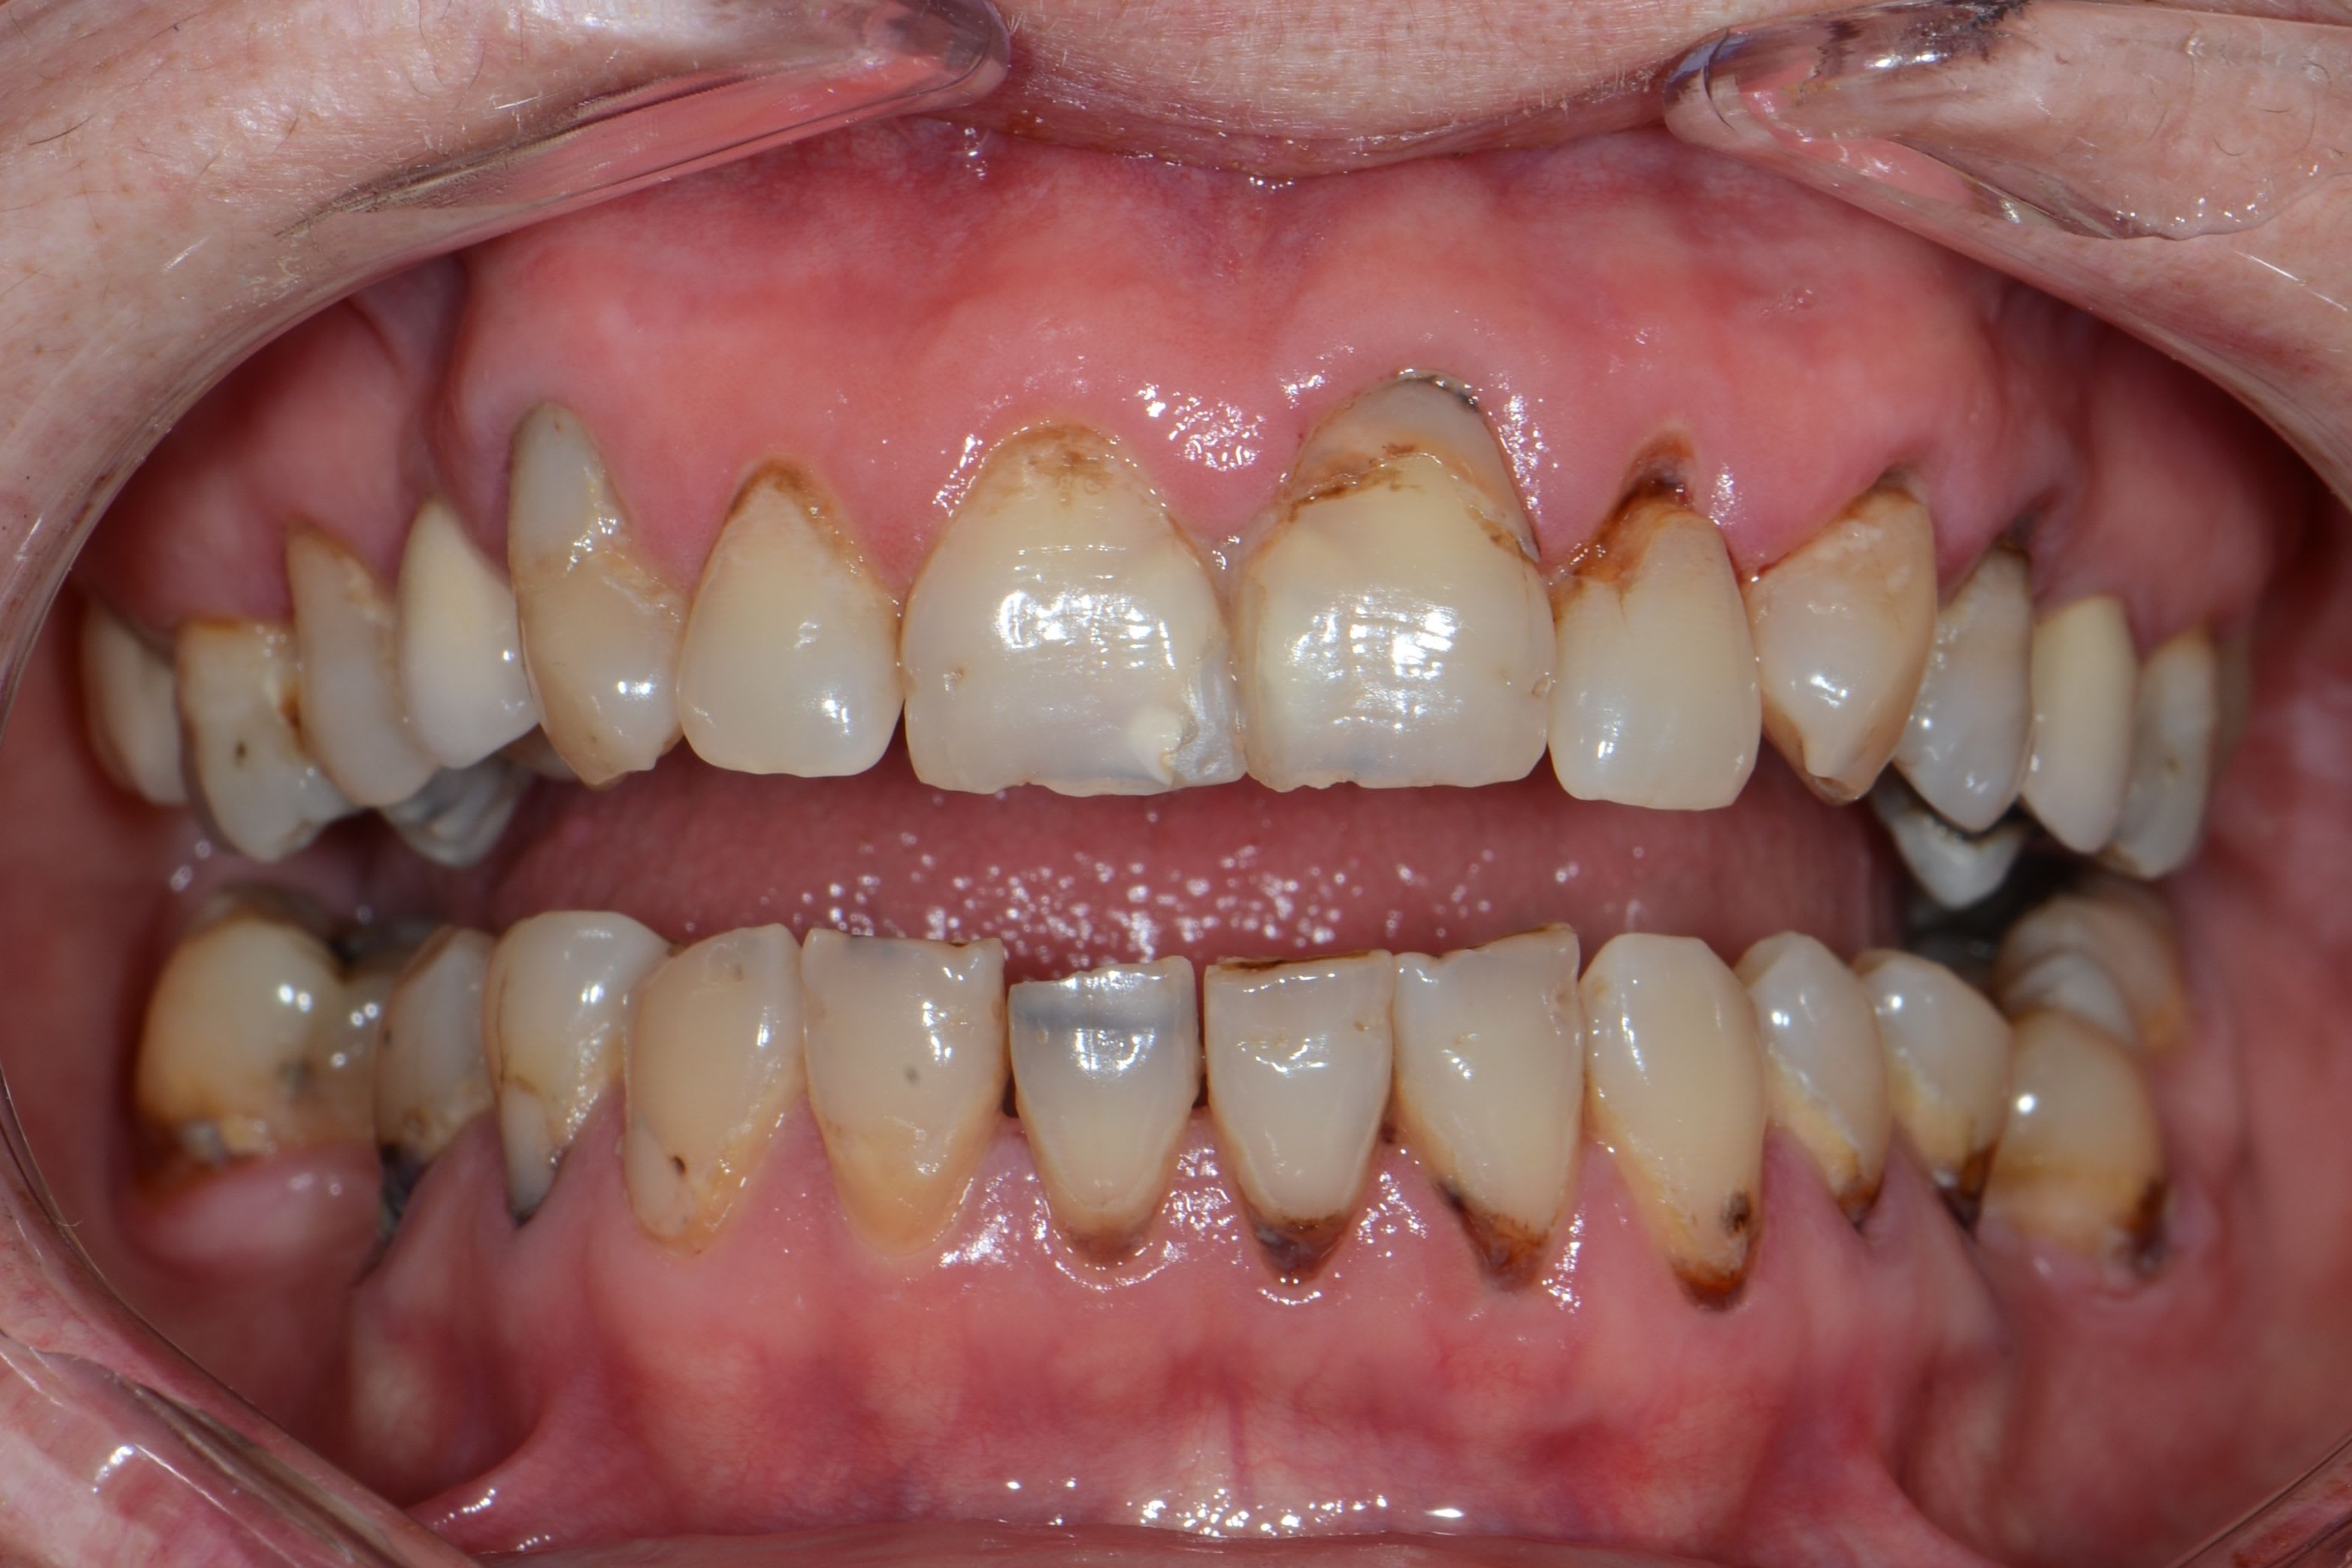

Nouvelle patiente 60 ans, pas de tabac, pas d'habitudes alimentaires prédisposantes mais syndrôme sec, très peu de salivation et ce depuis 2 ans.

A l'examen clinique, caries de collets typiques, la 45 a du être dévitalisée. Les caries sont plus importantes cliniquement que radiologiquement. Par ex les incisives mand étaient presque intégralement cariées en linguale (?).

Je lui ai fais un bilan et ai décidé de soigner les caries de collet au CVI (GC Equia forte). La 24 et 45 seront couronnées.